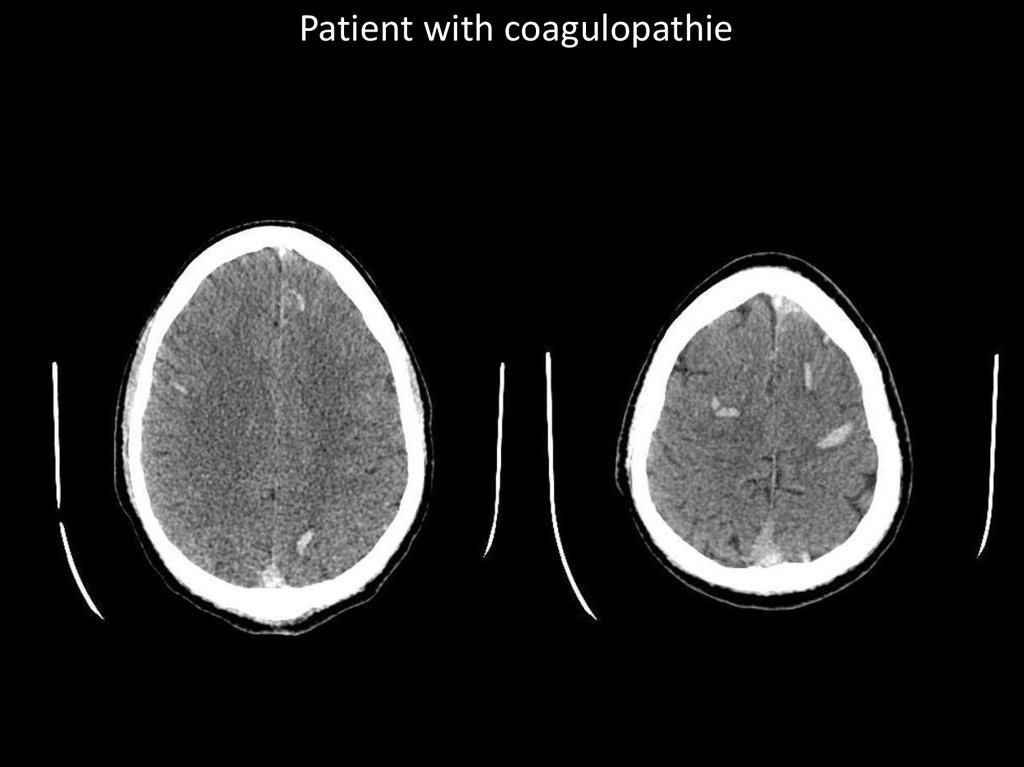

Patient with coagulopathie